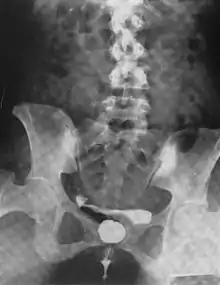

Urethral diverticulum is often an incidental finding.[2] It can be diagnosed using magnetic resonance imaging and/or micturating cystourethrography.[1] Other studies that can be used to diagnose urethral diverticulum include intravenous urography, urethroscopy, and/or ultrasound. Conditions that should be distinguished from urethral diverticulum in a differential diagnosis include overactive bladder, Gartner's duct cyst, Gartner's duct abscess, ectopic caeco-ureterocele, interstitial cystitis, pelvic inflammatory disease, endometriosis, and cancer.[3]